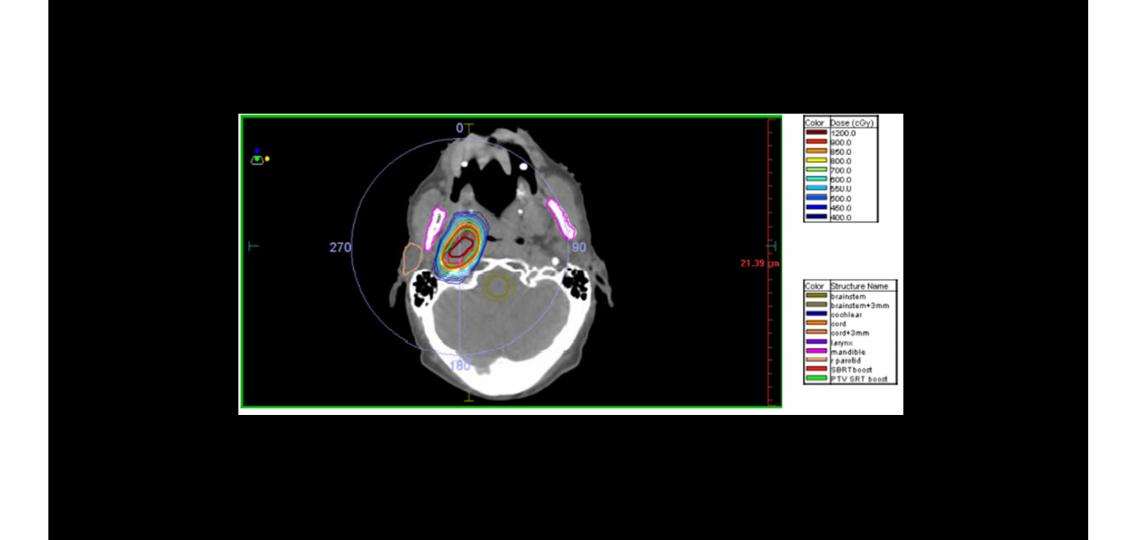

Stereotactic Radiotherapy for Head and Neck Cancer

Stereotactic body radiotherapy (SBRT) also known as stereotactic ablative radiotherapy (SABR) is a precise, painless, non-invasive radiation treatment that utilizes very accurately targeted, large “killing” doses of radiation. This non-invasive treatment has proven to be an effective alternative to surgery or conventional radiation for treating many small tumors and other select medical disorders. At the Baylor St. Luke’s Kirby Glen Radiation and CyberKnife facility, the CyberKnife system is utilized to deliver SBRT/SABR. It is the world’s first and only radiosurgery system designed to treat tumors anywhere in the body with sub-millimeter accuracy. Baylor St. Luke’s Radiation Therapy and CyberKnife Center is the only public center in Houston to offer CyberKnife radiosurgery.

Using image guidance technology and computer-controlled robotics, the CyberKnife system is designed to continually track, detect and correct for tumor and patient movement throughout the treatment. Because of its extreme precision, the CyberKnife system does not require invasive head or body frames to stabilize patient movement, vastly increasing the system’s flexibility. The CyberKnife procedure requires no anesthesia, can be performed on an outpatient basis and allows for the treatment of patients that otherwise would not have been treated with radiation or who may not have been good candidates for surgery. In addition, the CyberKnife procedure avoids many of the potential risks and complications that are associated with other treatment options.